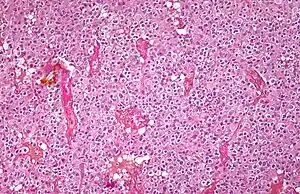

| Micrograph of an oligodendroglioma showing the characteristic branching, small, chicken wire-like blood vessels and fried egg-like cells, with clear cytoplasm and well-defined cell borders. H&E stain. | |

Oligodendrogliomas cannot currently be differentiated from other brain lesions solely by their clinical or radiographic appearance. As such, a brain biopsy is the only method of definitive diagnosis. Oligodendrogliomas recapitulate the appearance of the normal resident oligodendroglia of the brain. (Their name derives from the Greek roots 'oligo' meaning "few" and 'dendro' meaning "trees".) They are generally composed of cells with small to slightly enlarged round nuclei with dark, compact nuclei and a small amount of eosinophilic cytoplasm. They are often referred to as "fried egg" cells due to their histologic appearance. They appear as a monotonous population of mildly enlarged round cells infiltrating normal brain parenchyma and producing vague nodules. Although the tumor may appear to be vaguely circumscribed, it is by definition a diffusely infiltrating tumor.

Classically they tend to have a vasculature of finely branching capillaries that may take on a "chicken wire" appearance. When invading grey matter structures such as cortex, the neoplastic oligodendrocytes tend to cluster around neurons exhibiting a phenomenon referred to as "perineuronal satellitosis". Oligodendrogliomas may invade preferentially around vessels or under the pial surface of the brain.